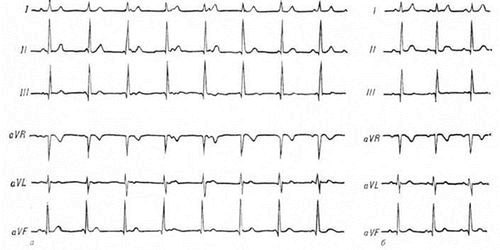

ЕКГ і УЗД серця - обов'язкові заходи навіть при ізольованій суглобової формі ревматизму.

Електрокардіограма (ЕКГ) - обов'язкова діагностична процедура навіть при ізольованій суглобової формі ревматизму